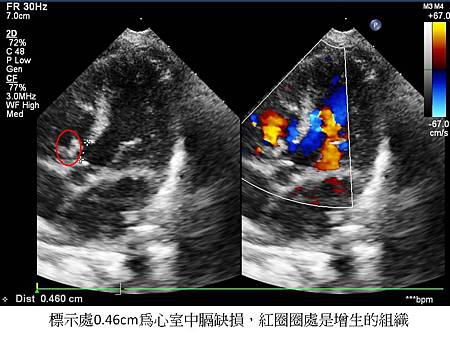

這個問題是家長接著最常問的問題。「心室中膈缺損」中,最常見的是第二型「心室中膈缺損」(膜邊型),這種有可能會在心室中膈缺損旁邊出現增生的組織,增生的組織長出來後,「心室中膈缺損」的洞就會變小、甚至癒合。